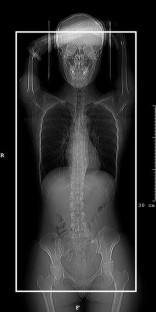

Polyarteritis nodosa: MDCT as a “One-Stop Shop” Modality for Whole-Body Arterial Evaluation

Polyarteritis nodosa is a rare disease, which is characterized by aneurysm formation and occlusion in the arteries of multiple systems. Due to its extensive involvement, whole-body evaluation is necessary for diagnosis and treatment monitoring. We report a case of polyarteritis nodosa using multidetector-row computed tomography (MDCT) as a “one-stop shop” modality for whole-body arterial evaluation. With precise protocol design, MDCT can be used as a reliable noninvasive modality providing comprehensive whole-body arterial evaluation.

Fig. 2